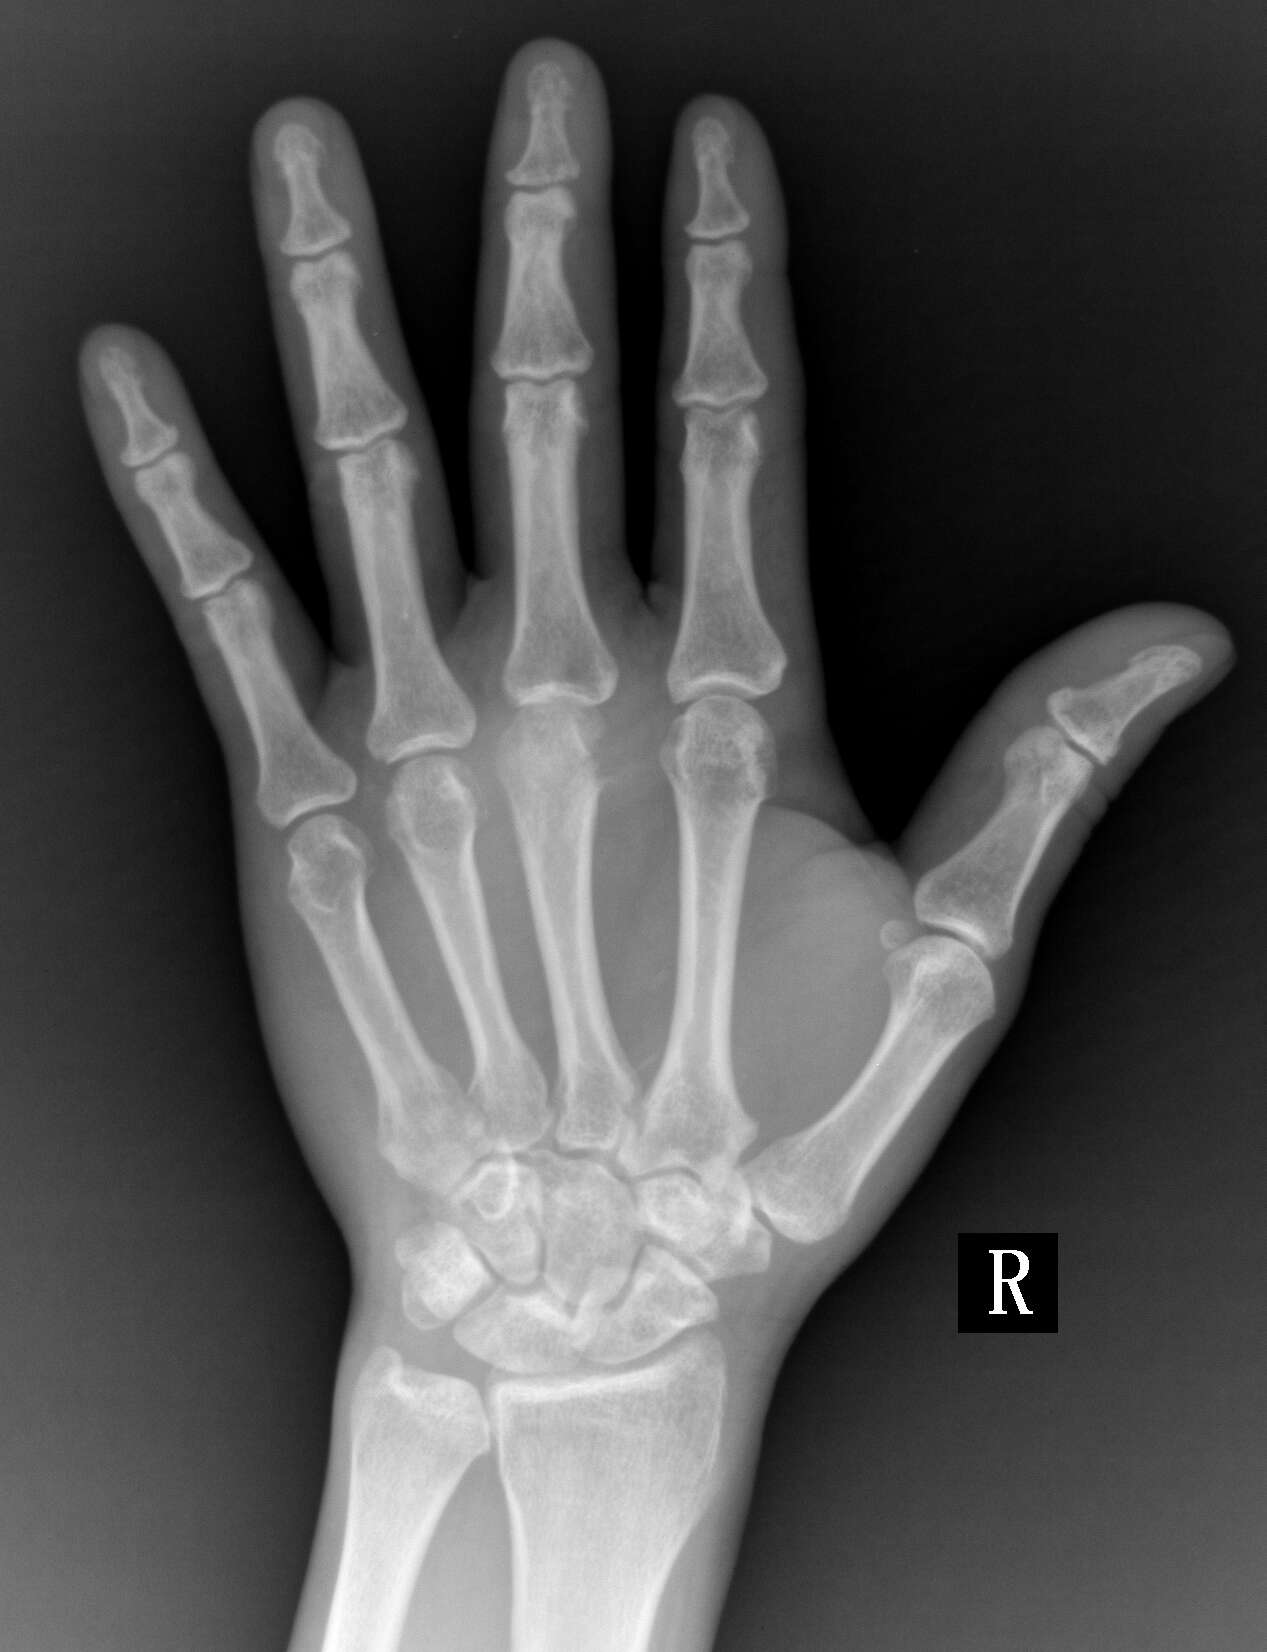

患者,男,47,右手背肿痛50天,皮肤有红肿,来拍片发现第三掌骨远端有骨质破坏,

化脓性关节炎可能性大

结合临床考虑第三掌指关节化脓性关节炎。

只有一个手指,结合临床症状,支持化脓性关节炎

考虑第三掌指关节化脓性关节炎。

单发骨边缘性骨质破坏,考虑骨结核可能性大。